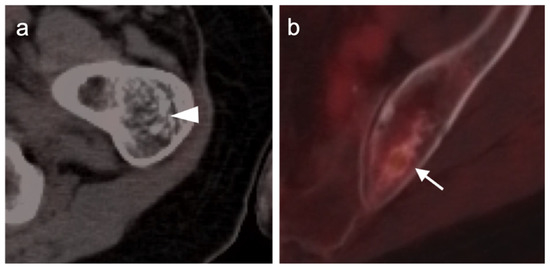

3.1.6. Liposarcoma

3.1.7. Synovial Sarcoma